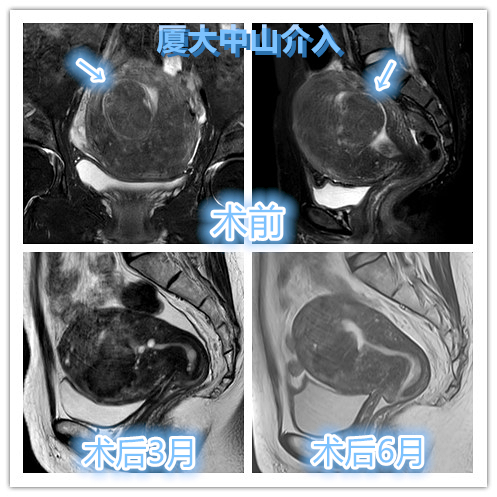

临床上大部分肌瘤在介入栓塞后,在MRI可以观察到病灶梗死,同时也观察到肌瘤位置出现多种变化,如粘膜下型肌瘤可发展为腔内肌瘤,浆膜下肌瘤可发展为肌壁间型或粘膜下型肌瘤。文献报道肌瘤向宫腔方向偏移的发生率高达37%,被称之为【肌瘤迁移】。

介入栓塞后出现子宫内膜不光滑表现与肌瘤脱落排出相关

这种变化机制容易导致介入栓塞术后出现慢性持续阴道分泌物。另外术后变化可能潜在对子宫内膜影响,继而可能对生育产生负面影响。这种情况下,对于希望怀孕的患友,妇科手术可能对生育影响会较小些,尤其是粘膜下型肌瘤可以通过宫腔镜手术切取,临床疗效确切。文献报道显示肌壁间肌瘤边缘距离子宫内膜<2.4mm,或者肌壁间肌瘤最大径>5.1cm,术后肌瘤容易移位至粘膜下或者脱落排出。因此术前需告知患友,注意术后可能出现肌瘤脱落、排出风险,及时复诊。

子宫腺肌病合并粘膜下肌瘤介入栓塞术后变化对比